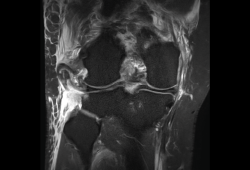

Figura 35. Corte de secuencia coronal y sagital de resonancia magnética de rodilla: rotura en asa de cubo del menisco interno con fragmento desplazado al intercóndilo.

1.2. Ligamentos

Se visualizan como estructuras lineales hipointensas en todas las secuencias.